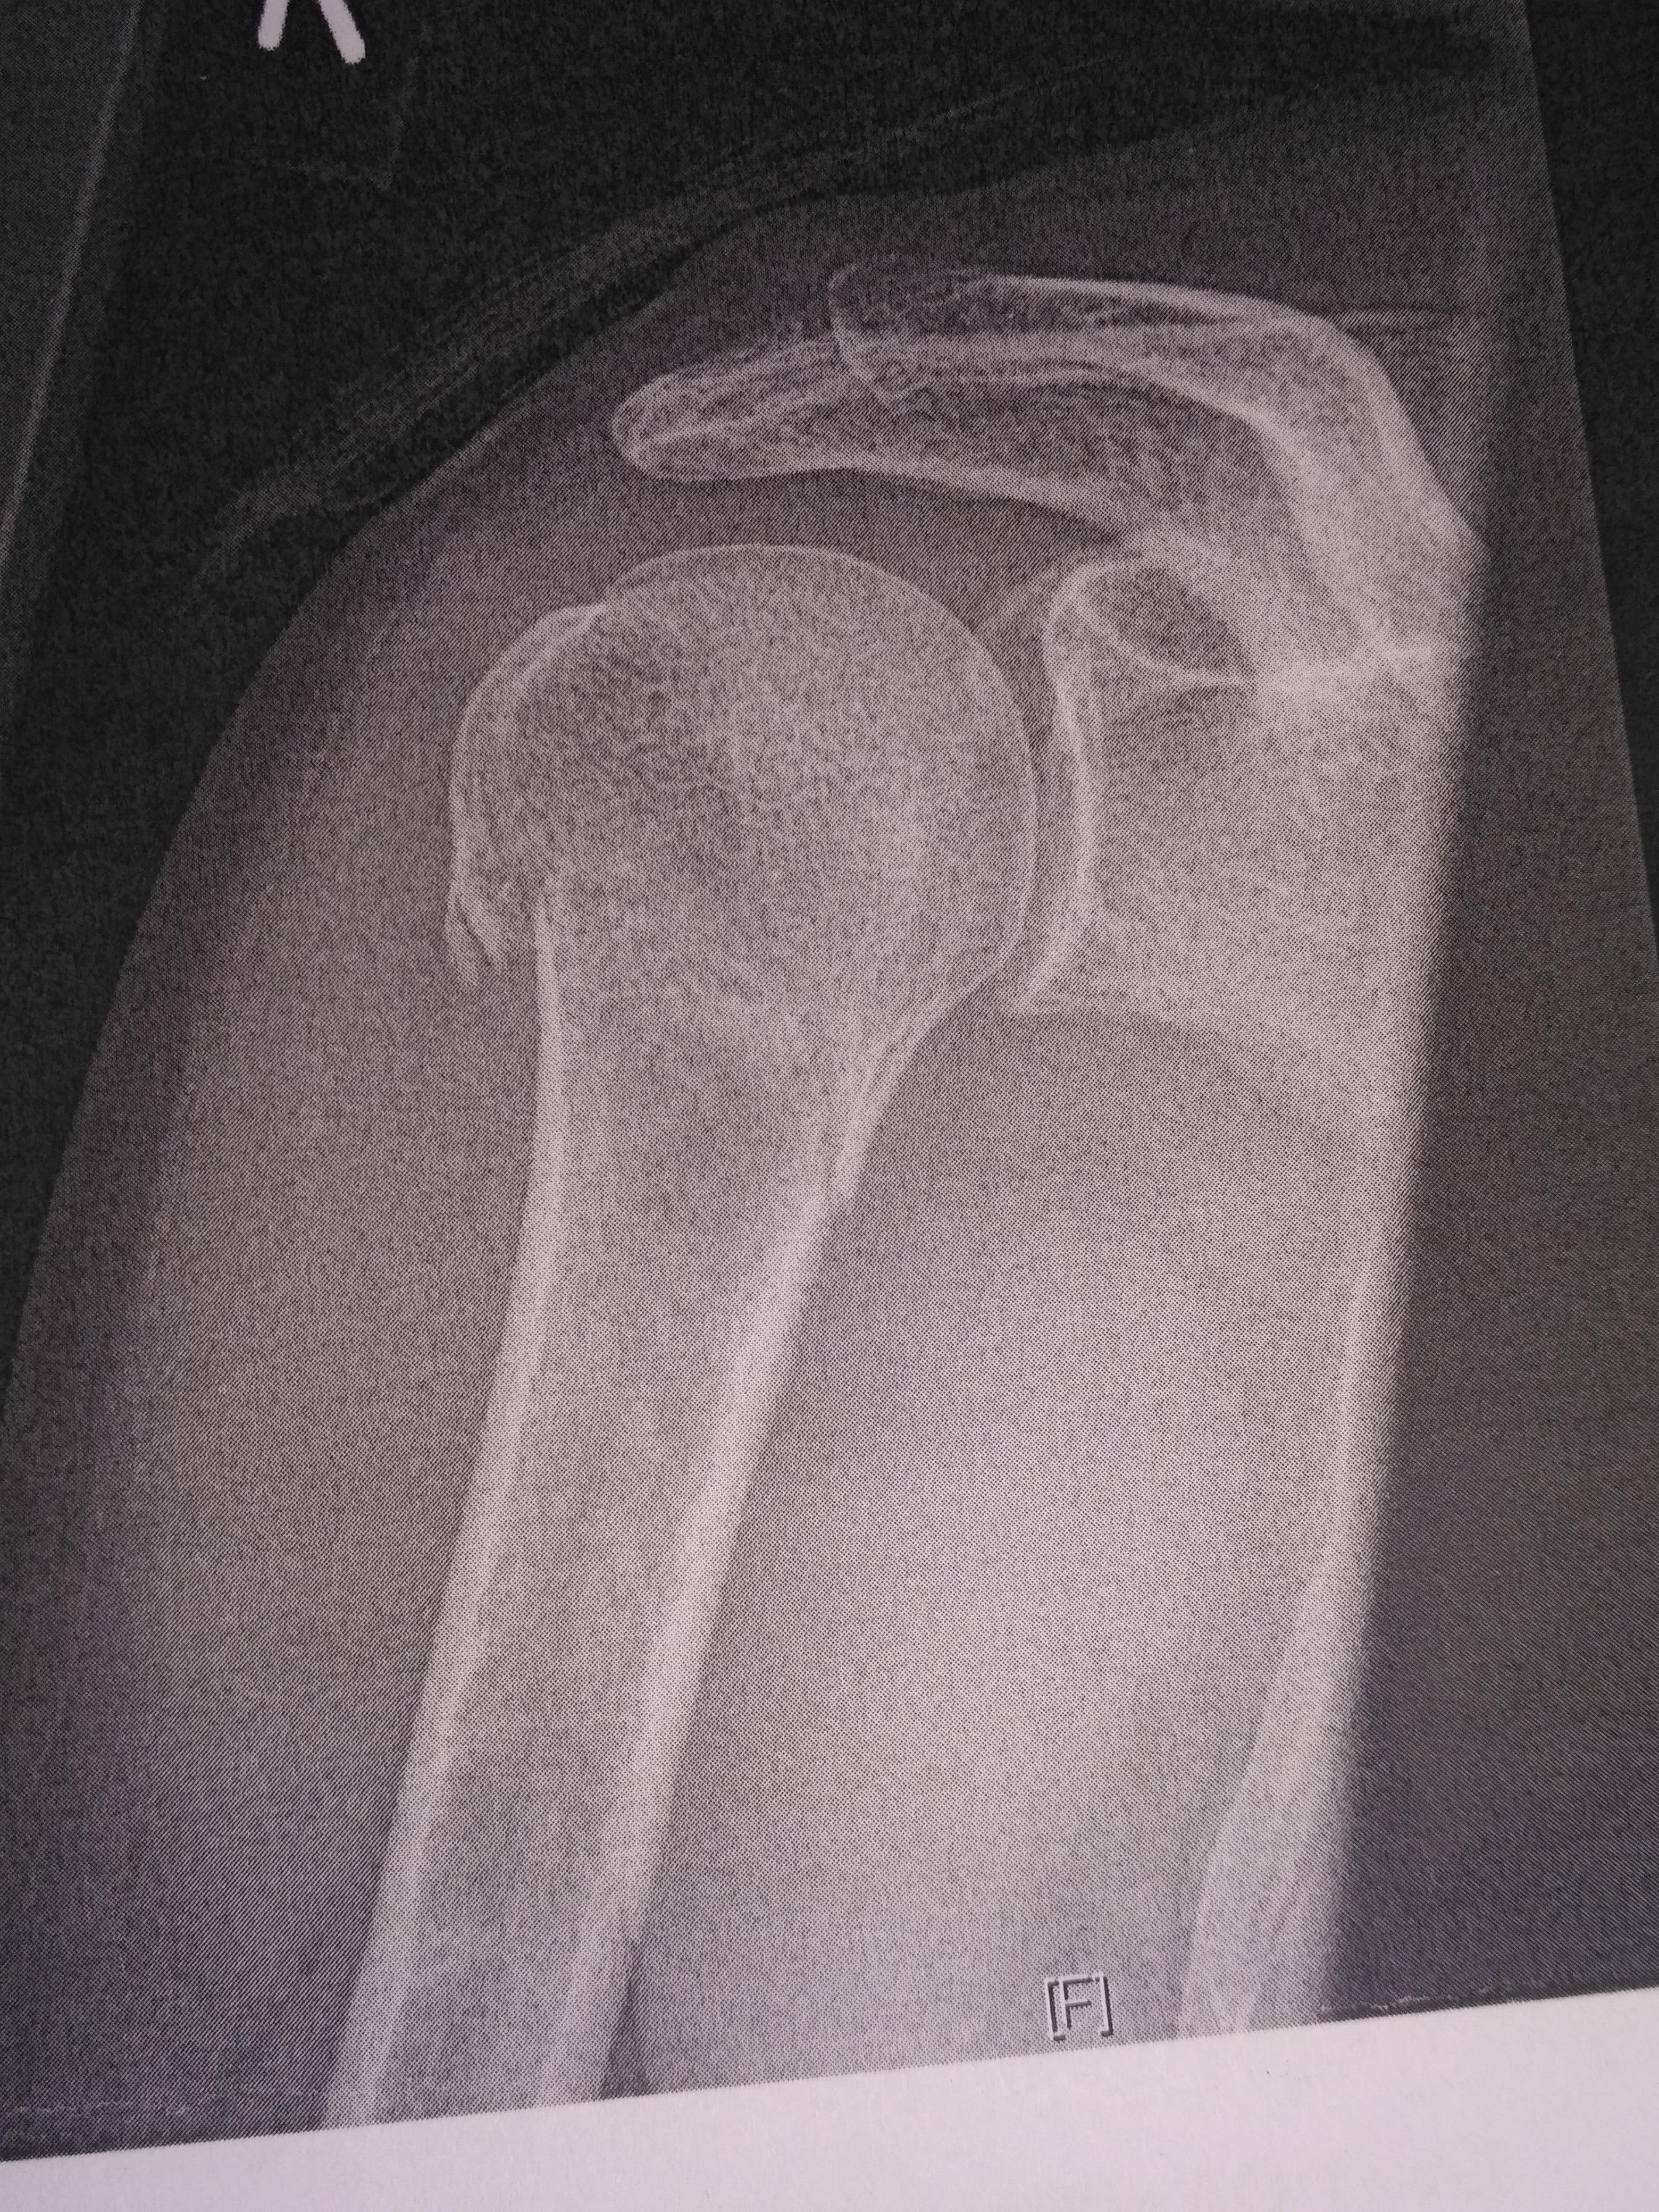

am 30.04.2018 hab ich (40+) mir durch einen Mountainbikeunfall den rechten Oberarm kurz unterhalb der Oberarmkopfes gebrochen.

Es war eine mehrfragmentäre Humerusfraktur mit Head Split rechts, und der Bruch wurde durch eine Plattenosteosynthese fixiert (siehe Foto).